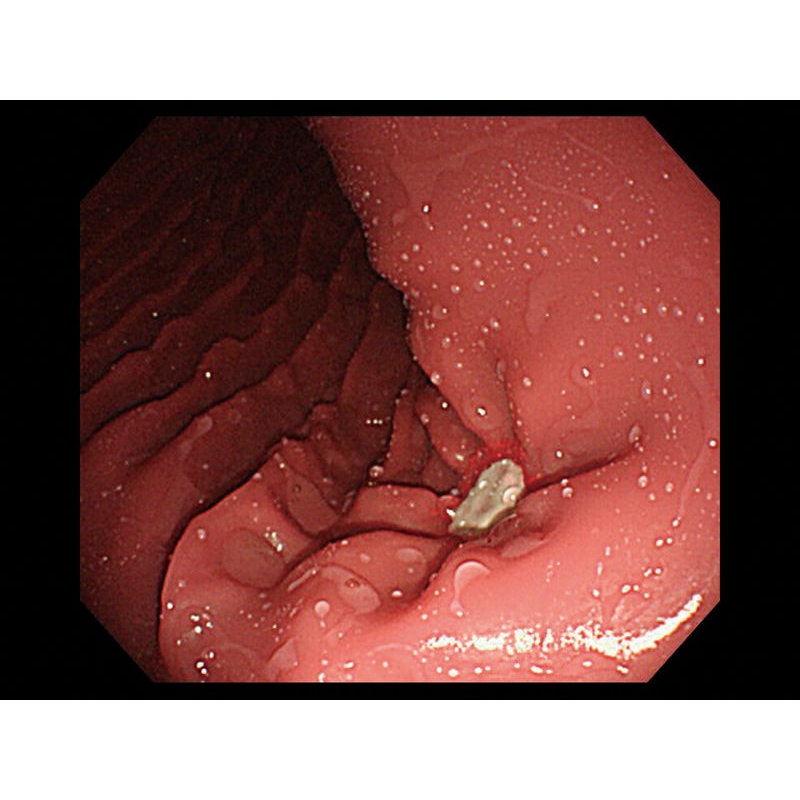

- V želodcu je mogoče opazovati želodčno razjedo in zgodnji rak želodca. Za opazovanje je mogoče pritrditi tudi štiri vrste polipov po Yamadovi klasifikaciji tipov od I do IV.

- V dvanajstniku je mogoče reproducirati razjedo.